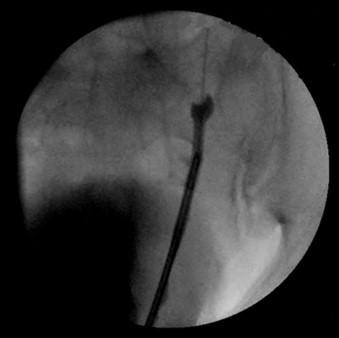

We present the case of a 70 year old man with a history of conservatively managed renal calculi, in whom obstructive ureterolithiasis was incidentally detected. Retrograde pyelography and ureteroscopy revealed intussusception of the ureter around a calculus. Extensive biopsies revealed no evidence of tumour, and the intussusception resolved following stone clearance.

我们报告一例70岁男性病例,其有保守治疗肾结石病史,偶然发现梗阻性输尿管结石。逆行肾盂造影和输尿管镜检查显示输尿管围绕结石发生套叠。广泛活检未发现肿瘤证据,结石清除后套叠得以缓解。